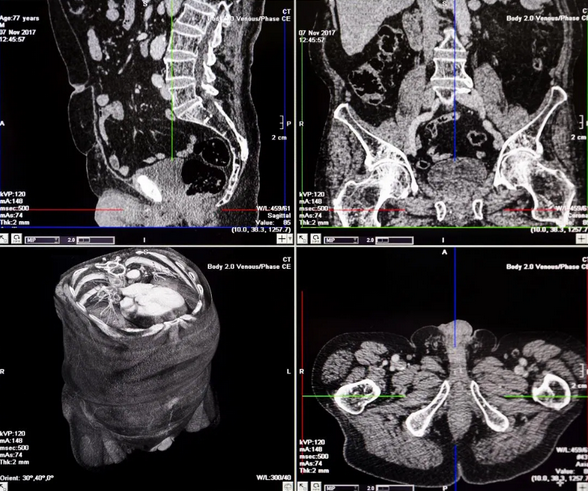

КТ брюшной полости является современным и точным рентгенологическим способом диагностики органов, расположенных в брюшной области. Во время обследования происходит томографическое, то есть, послойное сканирование исследуемой зоны. Современные мультспиральные томографы способны за один оборот сканера делать от 32 до 640 срезов, а мощный компьютер может создать трехмерные реконструкции всех анатомических структур области живота. Данные КТ снимков позволяют выявить воспалительные процессы и опухолевые изменения в костных и мягкотканных структурах.

Процедура компьютерной томографии органов брюшной полости проходит по двум базовым протоколам — нативная и контрастная. МСКТ с контрастным усилением предполагает использование контрастных препаратов на базе йода, которые улучшает тканевую контрастность на томограммах и позволяет определить новообразования на этапе развития. Кроме того, существует агиографическая форма обследования (КТ брюшной аорты и сосудов) области живота, когда врачи прицельно оценивают сосудистую систему брюшной полости.

Компьютерная томография, в отличие от базовой УЗИ и рентгена, максимально развернуто оценивает структуру ОБП. Такая диагностическая точность достигается за счет возможности делать множественные снимки с различных ракурсов. Принцип работы компьютерного томографа основывается на способности рентгеновских лучей проходить с разной скоростью через ткани различной плотности. Во время сканирования датчик рентгеновского излучателя движется по периметру кольца Гентри вокруг тела пациента. Пучки рентгеновских лучей проходят под разными ракурсами через ткани брюшной области, их остаточная мощность фиксируется приемником на другой стороне кольца. На базе этих данных компьютер томографа строит трёхмерные реконструкции.

КТ брюшной полости с контрастом способствует наиболее четкому отображению тканей и часто используется при онкопоиске. Контрастирование позволяет установить опухолевые очаги и степень их распространения на соседние участки. Контраст распространяется в крови и как бы “подкрашивает” ткани. Обязательного контрастного усиление потребует КТ ангиография сосудов брюшной полости. Без контрастирования сосудистая сеть на компьютерной томографии не видна.

Введение контрастного препарата происходит перед началом или в ходе процедуры, а полное вывод препарата из организма осуществляется естественным путем через мочевыделительную систему и занимает 48 часов. Продолжительность МСКТ с контрастом варьируется от 30 до 40 минут, в зависимости от способа применения контрастного вещества инъекционно уколом или болюсно, динамически.